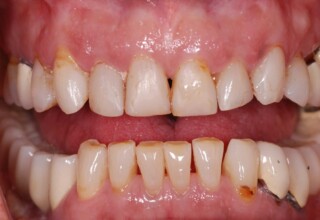

Extensive case with crowns in almost all teeth

Extensive case with crowns in almost all teeth due to extensive wear, old restorations, posterior root canals and aesthetic concerns. Patient (60years old) presented with intense bruxism which he never had treated. Consequently, he obtained very deep cervical abrasions which jeopardized tooth integrity. Restorations (fillings) were executed mainly with adhesive resinous materials and three custom cast post and cores. Temporary crowns were placed to evaluate the desired size, shape and position of the teeth before permanent crown fabrication.

Initial smile

Final Smile